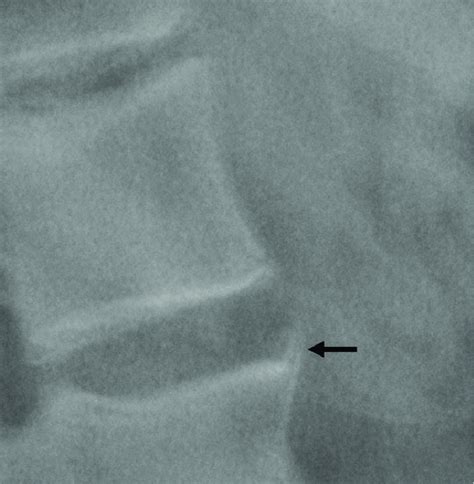

Finally, let’s talk about syndesmophytes . In pathology, particularly in the context of rheumatology and radiology, a syndesmophyte refers to a bony growth or calcification within a spinal ligament, specifically the outer fibers of the annulus fibrosus of the intervertebral disc. These bony growths are characteristically seen in certain types of inflammatory arthritis, most notably ankylosing spondylitis. They appear on X-rays as thin, vertical bony bridges connecting adjacent vertebrae. Unlike osteophytes, which are bony spurs that grow horizontally from the vertebral bodies, syndesmophytes grow vertically and are typically thinner and more delicate. They are a hallmark of axial spondyloarthritis and play a crucial role in diagnosing and monitoring the progression of the disease.

Radiologists play a crucial role in identifying syndesmophytes and differentiating them from other types of bony growths. The appearance of syndesmophytes on X-rays is often described as “marginal,” meaning that they originate at the edges of the vertebral bodies and extend vertically along the spine. This is in contrast to osteophytes, which are typically larger, more irregular in shape, and grow horizontally from the vertebral bodies. The distribution of syndesmophytes can also provide clues to the underlying diagnosis. In ankylosing spondylitis, syndesmophytes typically involve the entire spine, from the cervical to the lumbar region. However, in other conditions, such as psoriatic arthritis, syndesmophytes may be more patchy and asymmetrical.